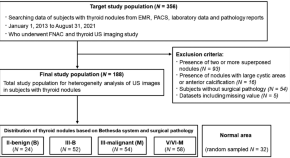

Differential diagnosis of thyroid nodules using heterogeneity quantification software on ultrasound images: correlation with the Bethesda system and surgical pathology

- Young Jae Ryu

- Jin Woong Kim

- Tae-Hoon Kim